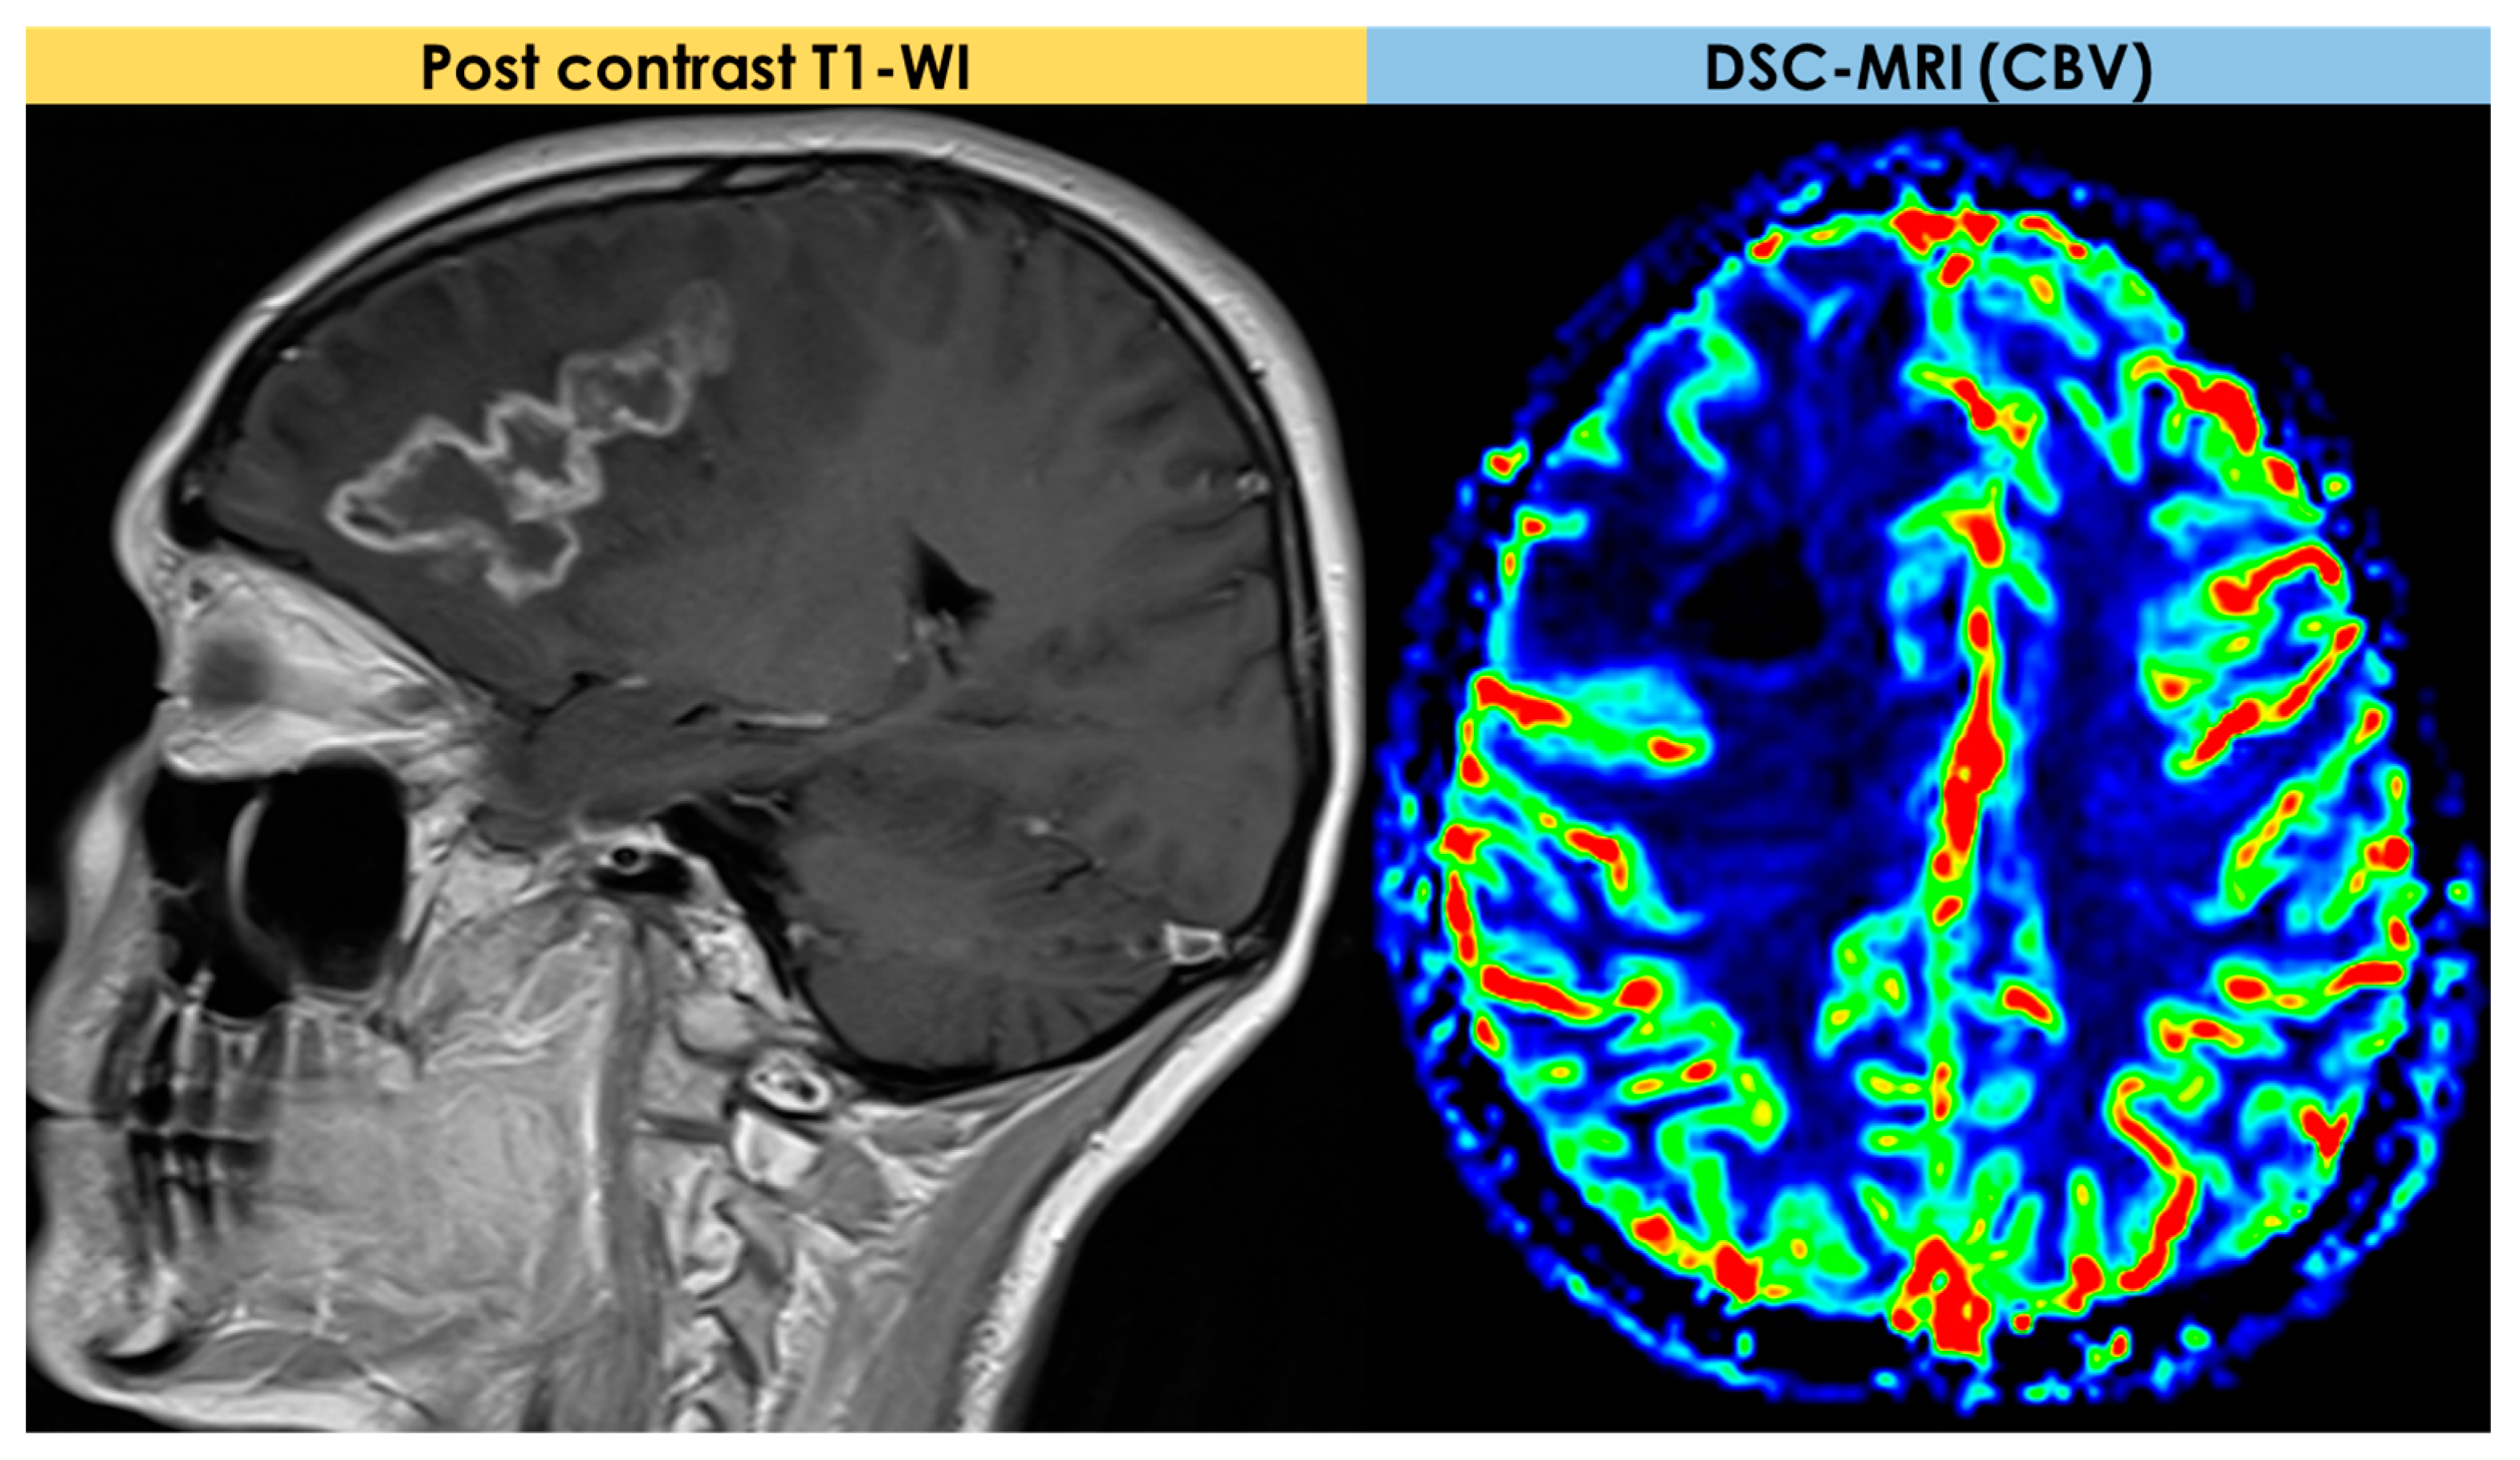

2.4. Advanced MRI Findings

- Dynamic susceptibility contrast (DSC) imaging, which is currently the most commonly used technique;

- Dynamic contrast-enhanced (DCE) imaging (both requiring intravenous administration of a gadolinium-based contrast medium);

- Arterial spin labeling (ASL), not requiring contrast media.